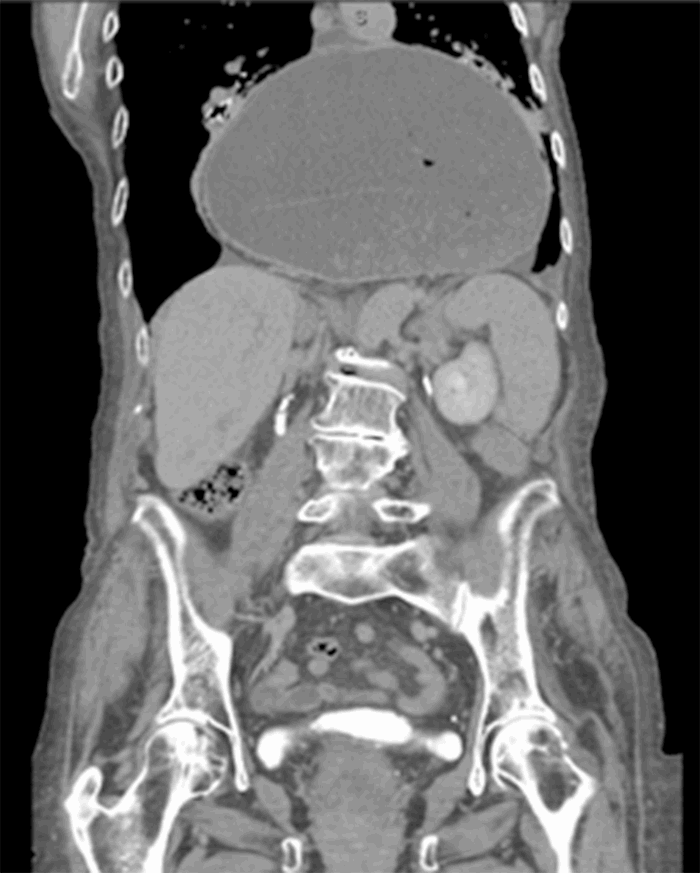

Computed tomography (CT) from outside facility performed earlier in the week revealed gastric outlet obstruction (GOO) caused by a massive type III PEH (Figure 1–4). She was subsequently discharged from this facility as she did not want surgical intervention and opted for hospice care. She presented to the ED later that week for persistent pain. At this time, it was decided to obtain a barium swallow instead of the repeat CT, demonstrating an intrathoracic stomach with concern for underlying gastric volvulus (Figure 5). Due to worsening obstructive symptoms, pain, and evidence of gastric outlet obstruction with possible gastric volvulus, it was recommended she undergo surgical intervention that day.

Figure 1. CT coronal view demonstrating large intrathoracic PEH.

Figure 2. CT coronal view demonstrating large intrathoracic PEH.